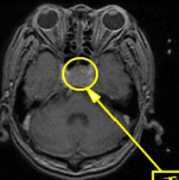

18岁花季少女突发闭经,脑内竟藏巨大危机! 起初,米拉只是月经迟迟不来,本以为只是内分泌失调,谁知医生却建议她前往神经外科检查。核磁共振结果令...